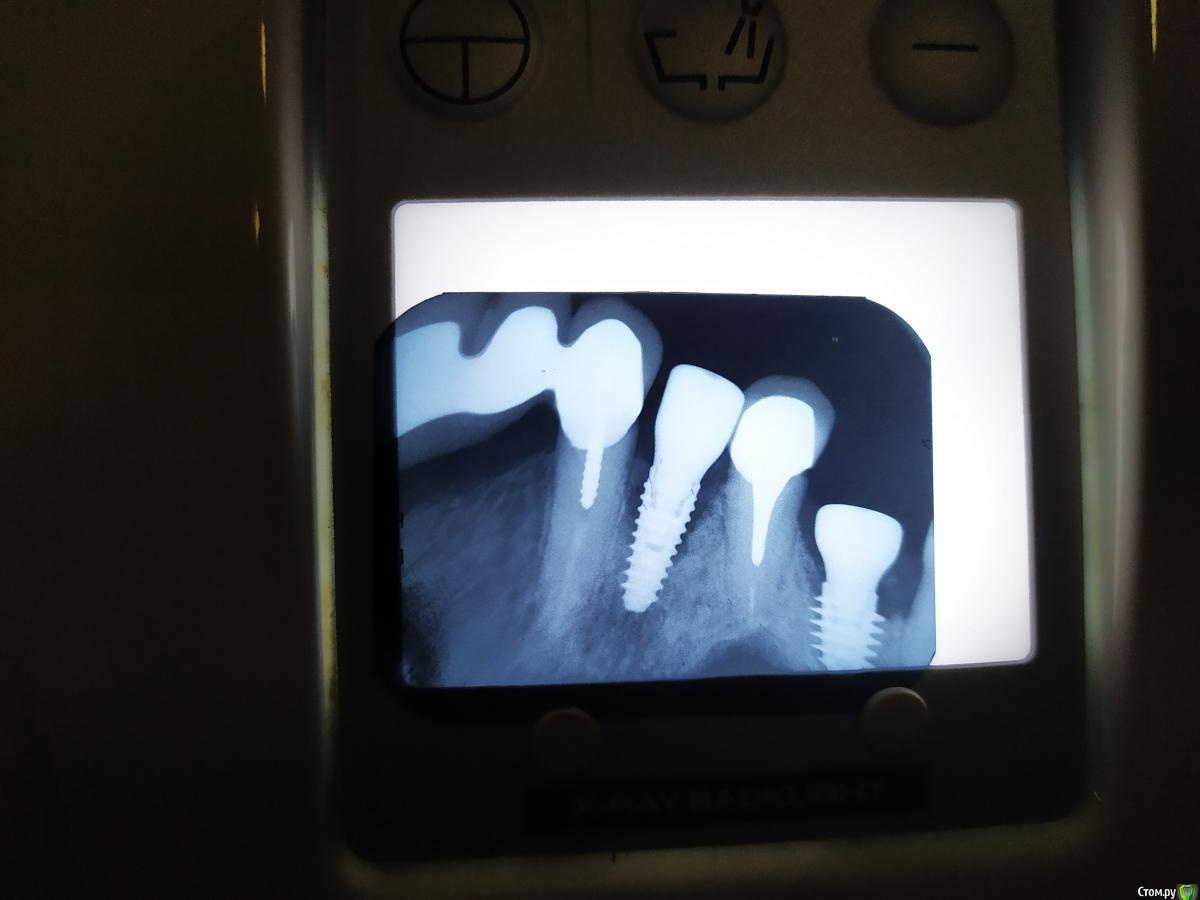

Aquarius Опубликовано 26 марта, 2020 Поделиться Опубликовано 26 марта, 2020 Коллеги, приветствую. Ваше мнение по ситуации. В декабре 19 г удаление 15,16 зубов с одномоментной имплантацией. Имплант 16 четко встал в межкорневую перегородку. Ушел в кость всем телом. В лунки корней - губка стимулл-осс. Через 3 месяца такая картина. Импланты-звонкие, ой-тест отрицательный, соматика у пациента не отягощена. Выкручивать?? Спасибо Ссылка на комментарий

Евгений Ходыкин Опубликовано 26 марта, 2020 Поделиться Опубликовано 26 марта, 2020 На ум приходит пока два момента:1) Чёткий ремоделинг кости, особенно учитывая отсутствие зубов рядом (нечему удерживать пучковую кость).2) Со стимул-оссом будь аккуратнее. Губка очень активная, сгусток впитывает на раз. Вполне могли быть явления вялотекущего альвеолита. По крайней мере я с ним обжигался в своей практике. 3) Всё вышесказанное - сугубое имхо 1 Ссылка на комментарий

Дмитрий Л. Опубликовано 26 марта, 2020 Поделиться Опубликовано 26 марта, 2020 Надо смотреть на высоту мягких тканей. Я думаю связано с объемом лунок корней. Надо было консервировать. Ссылка на комментарий

Aquarius Опубликовано 26 марта, 2020 Автор Поделиться Опубликовано 26 марта, 2020 (изменено) Надо смотреть на высоту мягких тканей. Я думаю связано с объемом лунок корней. Надо было консервировать.Высота небольшая. На шестерке около 2-3 мм. На пятёрке чуть чуть побольше Изменено 26 марта, 2020 пользователем Aquarius Ссылка на комментарий

EEcho Опубликовано 26 марта, 2020 Поделиться Опубликовано 26 марта, 2020 Естественная убыль, дистально нет костяшки и она естественно сгладилась. Надо было консервировать лунку или учитывать атрофию. Сейчас удалять не стоит, достаточно ССТ. + Временные коронки и наблюдение. Ссылка на комментарий